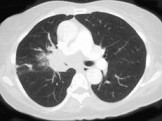

- 单项选择题男,56岁, 咳嗽,咯血1月余, 有吸烟史30余年,结合CT检查图, 选出最可能的诊断 ( )

E、中央型肺癌